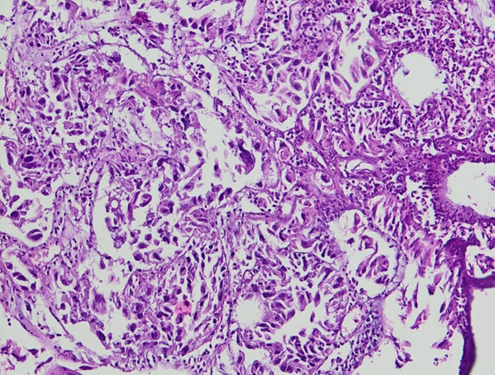

Figure 5. (HE x100)

Solid foci with polygonal cells, featuring rounded nuclei and large nucleoli, with abundant mitotic activity.

Figure 6. (HE x200)

The tumor cells are cuboidal or columnar, with pale or eosinophilic cytoplasm, round nuclei, and prominent nucleoli.